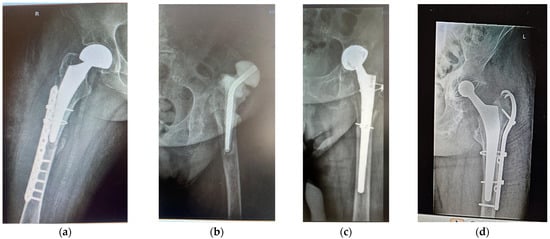

Case 1. A woman (F1) over 35 years old was admitted to the Clinical Emergency Hospital Bucharest (SCUB) with a basicervical femoral neck fracture (BCFNF), right side, following an unspecified fall on a flat surface. Her underlying conditions were as follows: Type 1 diabetes (insulin dependency); renal failure end stage (dialysis dependency); and essential hypertension. BCFNFs are rare, about 1.8% of all proximal femoral fractures, according to results from the comprehensive critical review by Jun-Il Yoo et al. [20]. Though F1 is a young patient, and BCFNFs are specific to the elderly, caused by low energy impact, her underlying conditions have contributed to bone weakness. In their review, which considers 15 studies, Jun-Il Yoo et al. conclude that definitions of BCFNF vary greatly, and, in consequence, treatment methods and their results also vary greatly. The treatment option for F1 was hemiarthroplasty with a bipolar prosthesis. During surgery, the patient suffered a periprosthetic fracture (Figure 1a) that needed cable fixation.

Figure 1.

Anterolateral radiographs of (a) patient F1 (primary HA; hemiarthroplasty with bipolar prosthesis); (b,c) patient F2, AHT revision after 15 years, with antibiotic spacer; (d) patient M, revision after 7 years, because of periprosthetic fracture and stem cracked 6 months before revision.

Case 2. A woman (F2) aged over 80 suffered an unspecified fall while performing housework at her home, resulting in a periprosthetic fracture of her left hip. The patient was admitted to the Clinical Emergency Hospital Bucharest (SCUB) for revision. F2 had suffered a left side THA 15 years earlier, at a different clinic, with a Zimmer implant. High blood pressure (AHT), dyslipidaemia, diabetes, hyper-uraemia, and hypothyroidism were her comorbidities. During the revision surgery, F2 was treated for prosthetic joint infection with an antibiotic spacer for three months. Prosthetic joint infections are mainly treated through a two-stage process [21,22], where infected implants are removed and antibiotic spacers are placed to preserve the length. When the site is free of infection, revision is performed. Figure 1b,c show the anteroposterior radiographs of F2’s revision THA.

Case 3. A over 65-year-old man (M) was admitted to the Clinical Emergency Hospital Bucharest (SCUB) for revision of a 7-year-old implant (THA). The patient had fallen on a hard surface and suffered a periprosthetic fracture. The stem cracked. M presented himself to hospital 6 months after the fracture was produced. His underlying conditions were very complex: AHT third degree, congestive heart failure, old myocardial infarction, coronary artery disease (CAD), atrioventricular block (AV) first degree, right bundle branch block (RBBB), dyslipidaemia (mixed hyperlipidaemia), and azotaemia. The cracked stem was extracted, and THA revision was performed using Zimmer Biomet Ti6Al4V stem (Figure 1d). Remnants of bone and soft periprosthetic tissue from the retrieved stem were collected for further investigations. The bone fragment exhibited a thin metal layer.

Anterolateral radiographs of the three cases are shown in Figure 1. F1 had a right-sided fracture, with primary HA (hemiarthroplasty with bipolar prosthesis). During surgery, a new fracture occurred, imposing supplementary fixation with cables. F2 and M underwent revisions on their left sides. All prosthetic elements were from Zimmer Biomet Romania SRL, Splaiul Independentei 319L, Paris Office Building, Corp A1, Ground Floor, Bucharest, Romania.